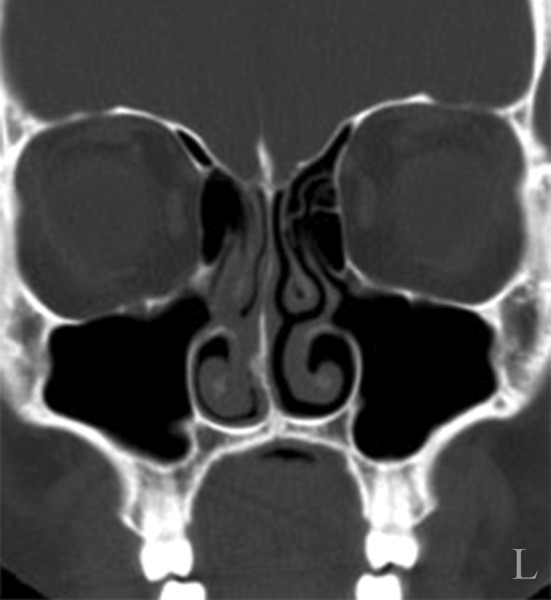

Fig. 4.

CT scan used for result evaluation showing the continuity of the sinus floor